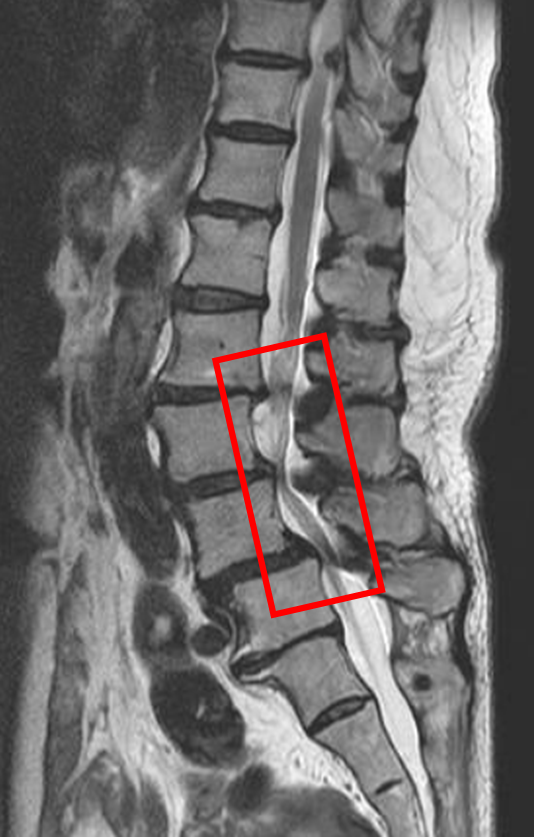

この患者様は赤い枠で示されている箇所(L2/3,3/4,4/5)に脊柱管狭窄症を認めます。